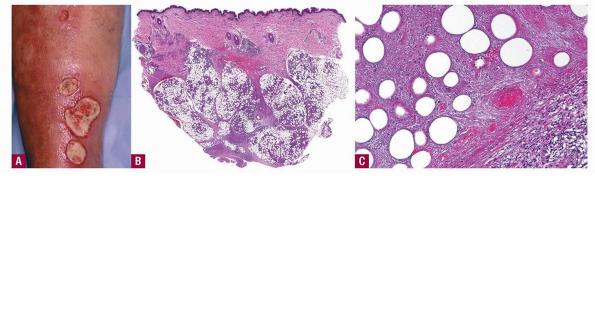

The lesions of erythema induratum, also sometimes referred to as nodular vasculitis, consist of painless to tender, deep-seated, circumscribed nodules to plaques, usually on the lower legs with a predilection for the posterior calves. Gradually, the lesions extend toward the surface, forming blue-red plaques that can ulcerate before healing with atrophy and scarring

In contrast to erythema nodosum that is mainly a septal panniculitis, erythema induratum (nodular vasculitis) initially is mainly a lobular panniculitis due to vasculitis that produces ischemic necrosis of the fat

lobules with relatively less involvement of the structures of the septa. The fat necrosis can be extensive, caseous as well as coagulative, and elicits granulomatous inflammation . Epithelioid cells and giant cells form broad zones of inflammation surrounding the necrosis but also can form well-delimited granulomas of the tuberculoid type . Ziehl-Neelsen stains do not reveal intact mycobacteria . In approximately one third of cases, granulomas are sparse or absent and lymphocytes and plasma cells predominate . Both the tuberculoid granulomas and lymphoid infiltrate extend between the fat cells, largely replacing them.

Vascular changes are extensive and severe. Arteries and veins of small and medium size show infiltration of their walls by a dense lymphoid or granulomatous inflammatory infiltrate  associated with endothelial swelling and edema of the vessel walls and fibrous thickening of the intima .

Thrombosis and occlusion, or just compromise, of the lumen can produce extensive ischemic and caseous necrosis of the fat in about half of the cases . Extensive necrosis leads to involvement of the overlying dermis and subsequent ulceration. The necrotic fat contains large fat globules, with surrounding amorphous, finely granular, eosinophilic material with some pyknotic nuclei. Later lesions contain many foamy histiocytes surrounding areas of fat necrosis.